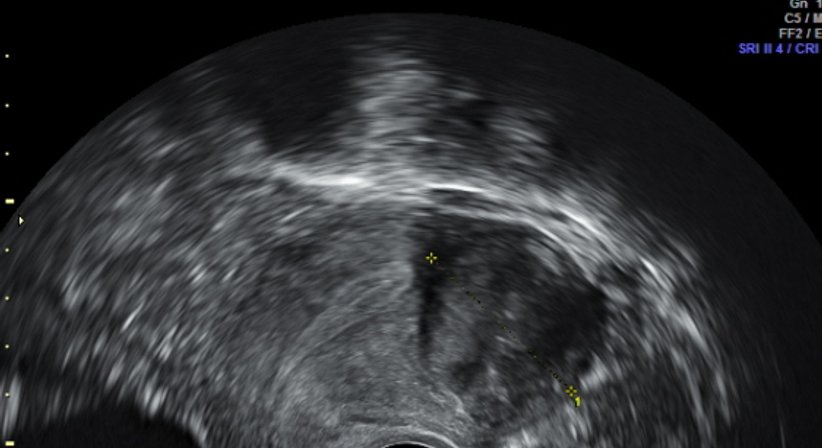

Myome der Gebärmutter:

Myome sind gutartige Muskelknoten, die von der Gebärmutter ausgehen. Nur ganz selten können sie bösartig entarten. Ungefähr ein Drittel aller Frauen bekommen Myome, eine gewisse familiäre Häufung ist zu sehen. Wie solche Myome entstehen ist noch relativ unklar, aber man weiß, dass sie hormonell gesteuert werden. Je nach Größe und Leidensdruck aufgrund von Schmerzen und/oder Blutungen ist die kausale Therapie die operative Entfernung der Myome, allerdings kommt es nicht selten zu so genannten rezidiven, also neu entstehende Knoten.